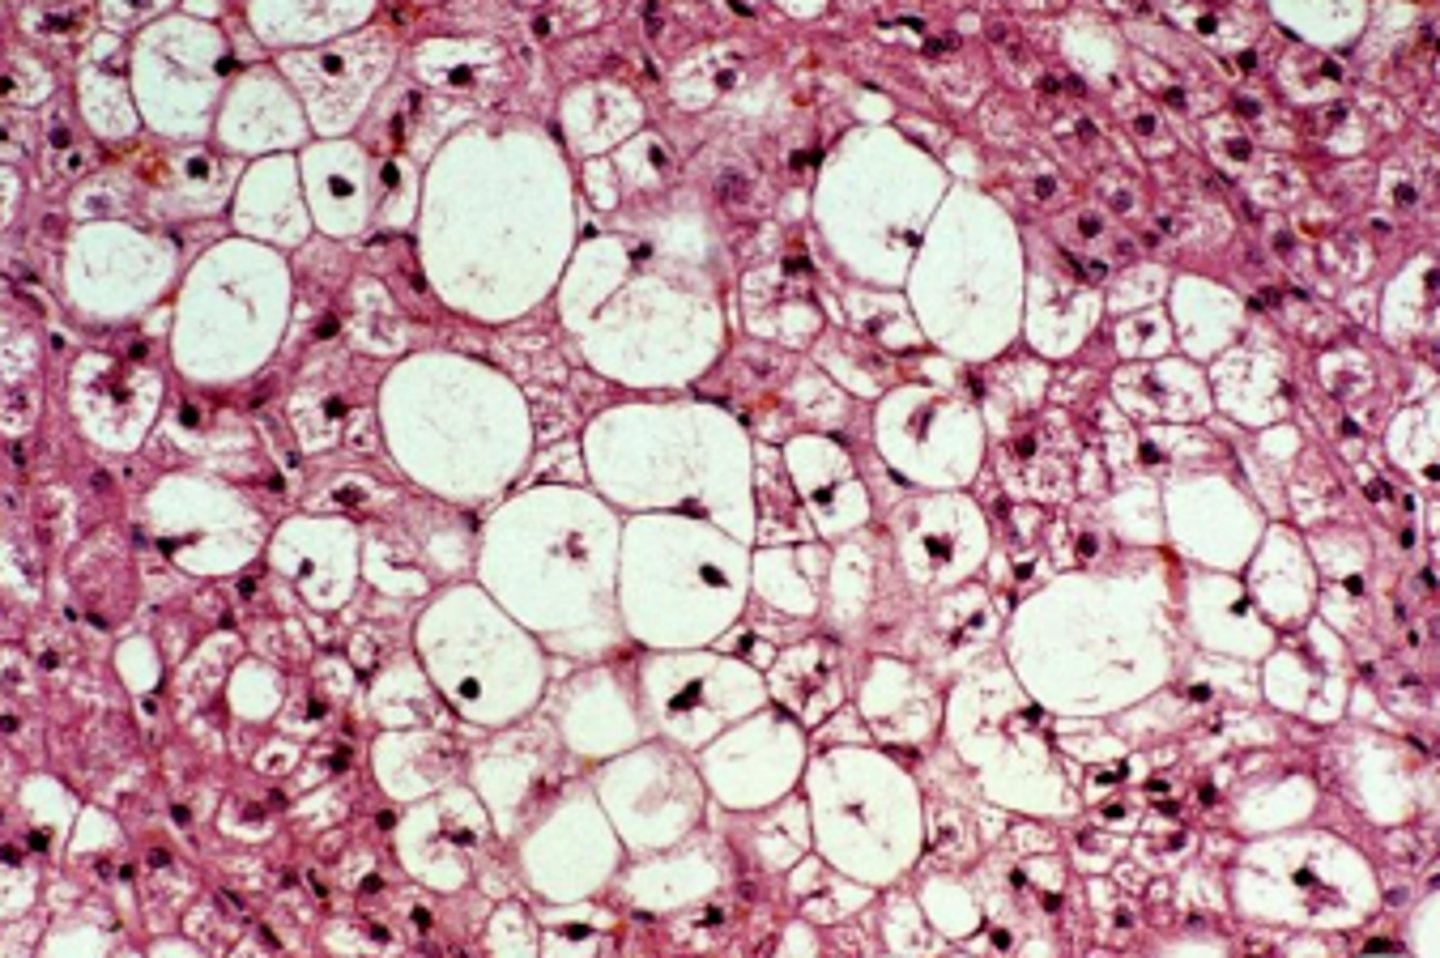

glycogen or lipid?

glycogen

central nuclei, some webbing

<p>glycogen</p><p>central nuclei, some webbing</p>

how does glycogen appear microscopically?

clear granules, vacuoles

less sharply defined than lipid and less likely to displace nucleus

<p>clear granules, vacuoles</p><p>less sharply defined than lipid and less likely to displace nucleus</p>